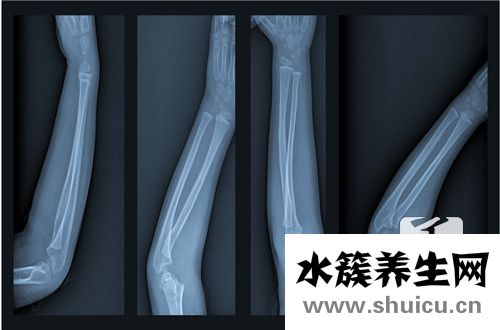

右撓骨遠端骨折在生活當中比較常見,占總的骨折大約1/10左右.多見一些中老年人,尤其是老年女性,因為骨質(zhì)疏松的原因,很可能發(fā)生這個部位發(fā)生骨折,相對來說是比較嚴重的,因為發(fā)生骨折以后會導(dǎo)致脹痛等現(xiàn)...